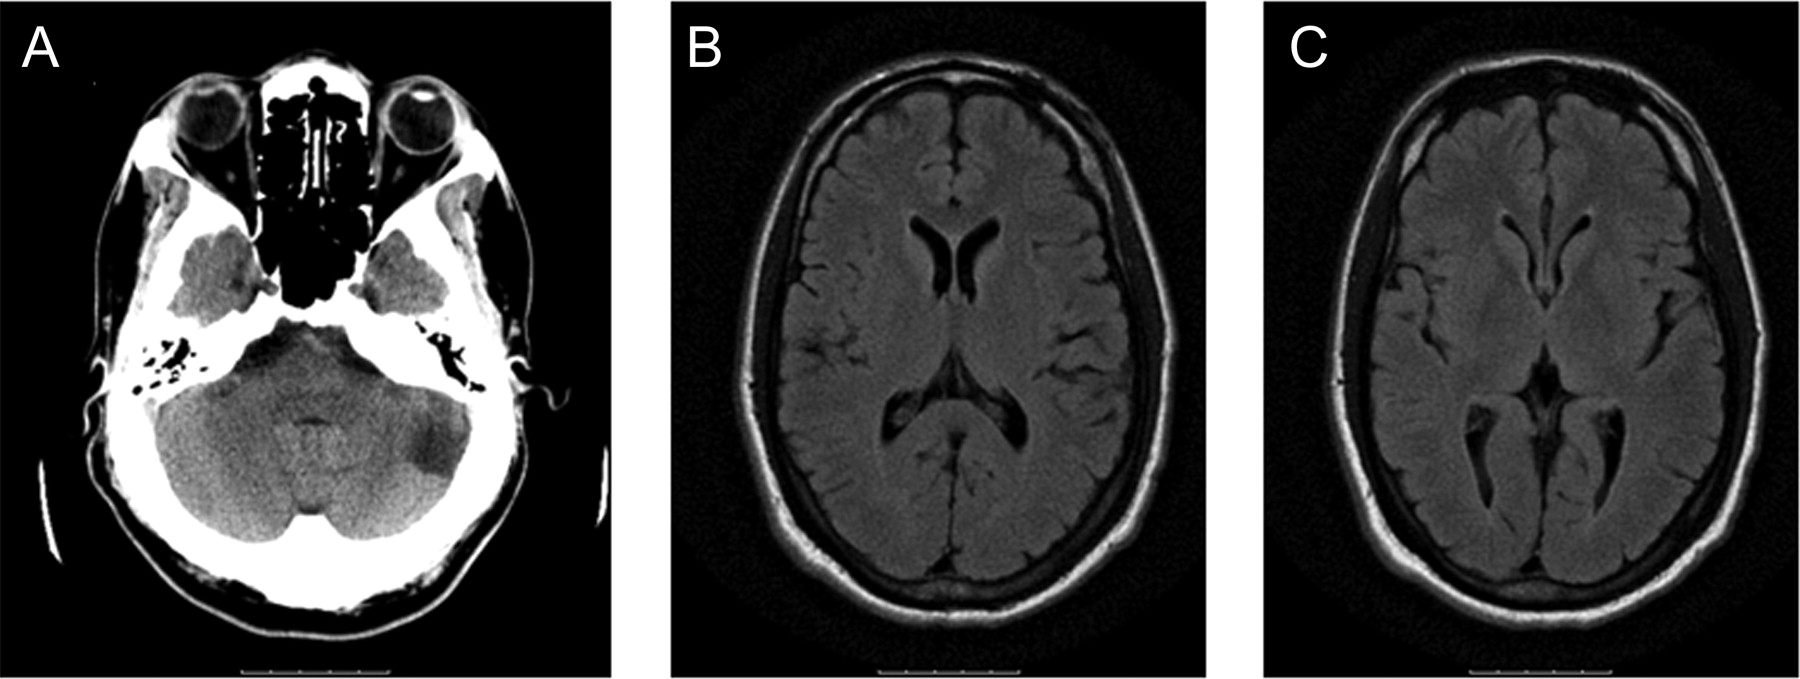

实验室测试包括一个完整的血细胞计数、血清化学、凝固面板,肝功能测试是正常的。心电图显示正常窦性心律和左心室肥大的证据。核磁共振成像显示,没有证据表明急性颅内异常;一种慢性左小脑梗塞是(图1)。CT血管造影显示严重双侧大脑中动脉(MCA)狭窄,更糟糕的是在右边,以及一个没有左椎动脉由传统血管摄影证实(图2一个)。

头部CT (A)在入学证明慢性左小脑梗塞。Fluid-attenuated反转恢复(天赋)MRI入院时没有证据显示大脑中动脉缺血性改变领土(B),天赋也负(C)。